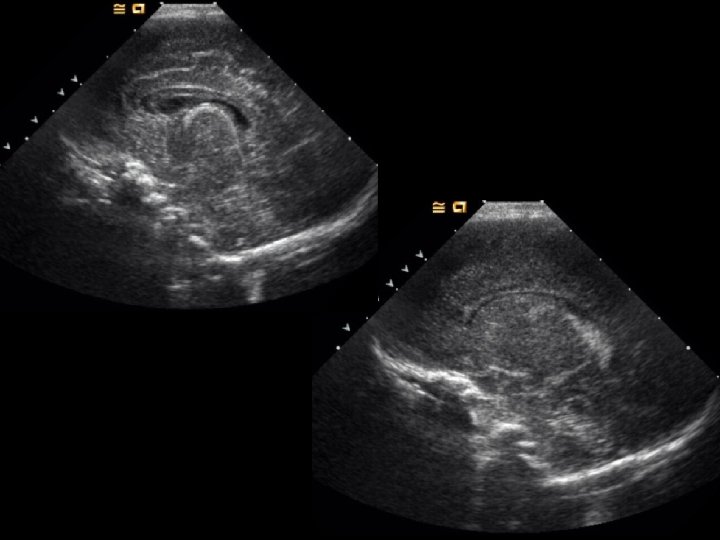

ADPKD • Findings: – Enlarged bilateral kidneys containing innumerable cysts – May also see hepatic cysts – Cysts complicated by hemorrhage or infection – NO increase risk of RCC • ddx: – NONE! – This is an Aunt Minnie!